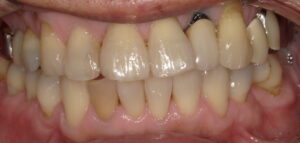

患者さんは50代男性。右下二番目の歯の変色が気になるとのこと。大きく削らずに治したいと希望があったためウォーキングブリーチを選択しました。

術前:右下2番目(正面から見て左下前から2番目)の歯に変色が見られます。